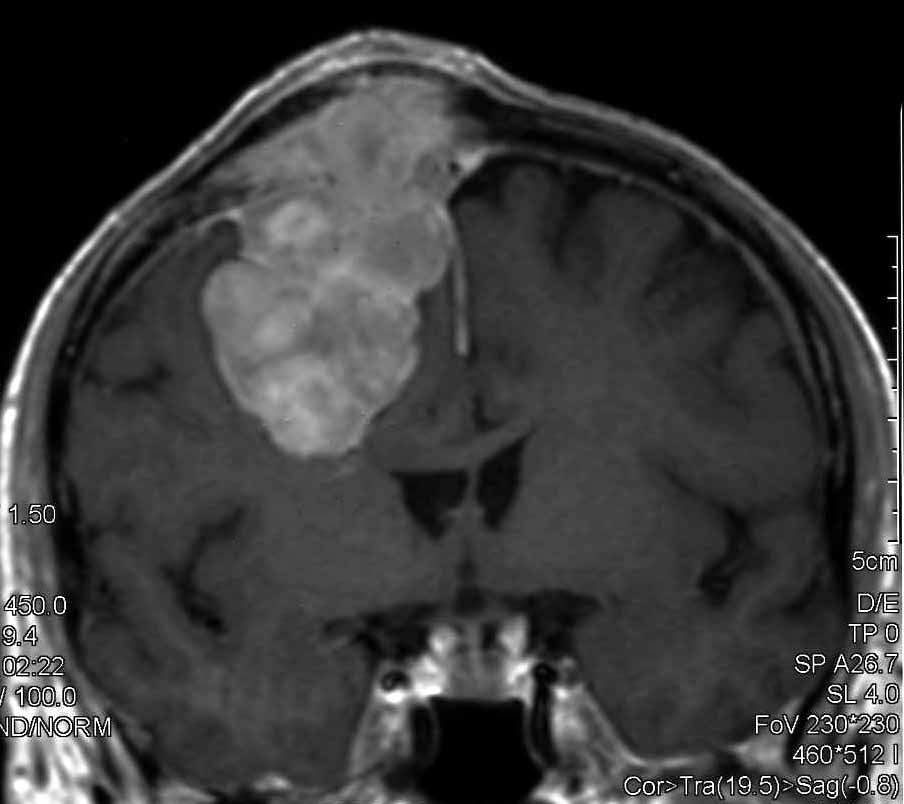

Meningioma |

| Meningioma

con demolizione-ricostruzione della teca cranica in un unico tempo

con tecnica microchirurgica e neuronavigazione. |